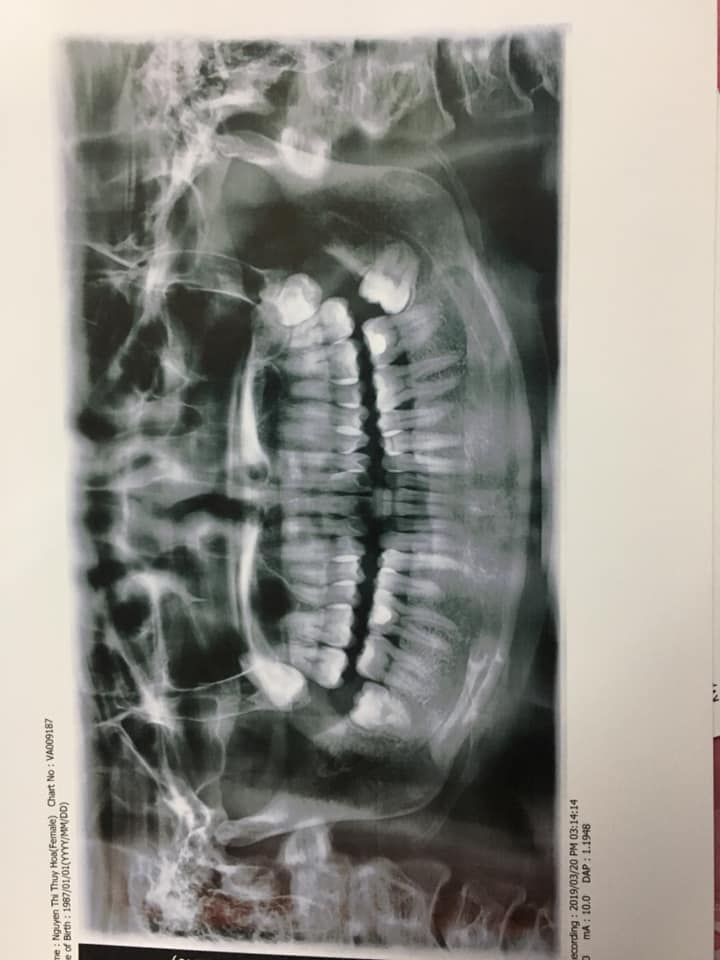

Em có 2 răng cửa thưa và chìa ra ngoài thế kia, hàm dưới hơi chìa 1 tí; khớp cắn ok nhưng Thái dương bị hóp sẵn ạ. Em đi khám bsi tư vấn 2 phương án: 1. Là nhổ 4r hàm nhỏ lấy khoảng kéo, 4 răng số 8 thì theo dõi nhổ sau; thì có thể mặt nghiêng niềng xong sẽ đẹp hơn, cằm Vline hơn. Nhưng em gầy lắm, 42 kg, cơ địa cực khó tăng cân. Thái dương lại hóp sẵn nên e sợ nhổ răng sẽ bị hóp nặng thêm lại như cái hình xương chéo người ta sơn ngoài cột điện, sợ mặt sẽ không đẹp dù răng có đẹp lên. 2. Nhổ ngay 4 răng số 8, và cắt kẽ, kết hợp chỉnh cung răng, đóng khe thưa, thì chỉ giảm hô được tầm 30% nhưng vì mặt nghiêng không hô mà chỉ cười nghiêng thì chìa ra thôi, cho nên 30% vẫn chấp nhận được. Tuy nhiên, không biết xong thì sẽ thành thế nào. Mong các bác sĩ tư vấn thêm ạ